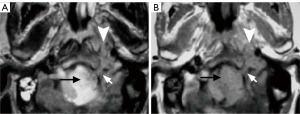

Paragangliomas have characteristic CT and MRI appearances based on their hypervascularity. They are usually homogeneously or heterogeneously hyperdense or hyperintense after contrast enhancement, with incorporation of adjacent arteries on CT and MRI (Figures 10-12) (12). On MRI, serpentine and punctate areas of signal void representing high vascular flow are interspersed with areas of high signal intensity caused by slowly flowing blood. This “salt-and-pepper” pattern is seen in all lesions greater than 2 cm in maximal dimension (Figure 11) (23-25). Carotid body tumors (paragangliomas of the carotid body) splay the ICA and the external carotid artery (ECA) and may encase the ICA and ECA (Figure 10), whereas vagal paragangliomas displace both ICA and ECA anteromedially, separating these vessels from the IJV (Figure 11). Paragangliomas may be multicentric and can manifest as unilateral or bilateral lesions, either simultaneously or sequentially. Only a very low percentage of 3% of paragangliomas will undergo malignant transformation (25). The presence of local lymph node involvement, distant metastases, or extensive local invasion will establish the malignancy of a paraganglioma.

In the past, digital subtraction angiography (DSA) played an important role as a first-line imaging investigation for paragangliomas (26). However, such an invasive method is reserved for those few patients whose diagnosis, after sectional imaging, remains inconclusive, or preoperative embolization. DSA, and sometimes computed tomography angiography (CTA), will show feeding arteries, such as the ascending pharyngeal artery (the artery of the paraganglioma) (Figure 12) and occipital artery (27). DSA also shows intense staining of the tumor and a rapid venous drainage.